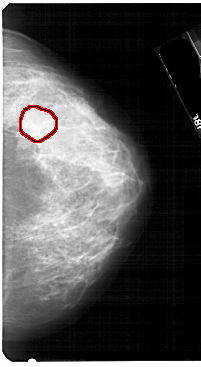

A_1752_1.LEFT_MLO

LEFT_MLO LINES 5491 PIXELS_PER_LINE 3421 BITS_PER_PIXEL 12 RESOLUTION 43.5 NON_OVERLAY

RIGHT_MLO LINES 5491 PIXELS_PER_LINE 3511 BITS_PER_PIXEL 12 RESOLUTION 43.5 OVERLAY

FILE: A_1752_1.RIGHT_MLO.OVERLAY

TOTAL_ABNORMALITIES 1

ABNORMALITY 1

LESION_TYPE MASS SHAPE LOBULATED MARGINS OBSCURED

ASSESSMENT 4

SUBTLETY 2

PATHOLOGY BENIGN

TOTAL_OUTLINES 1

BOUNDARY